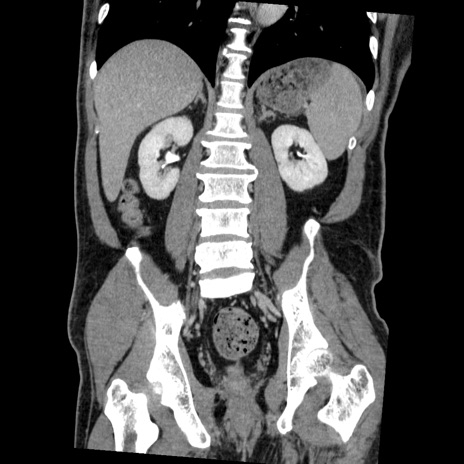

症例22(冠状断像)

【症例】50歳代男性

【主訴】腹痛

【現病歴】AVMからの被殻出血のため回復期リハ病棟入院中。 本日午後3時頃急に下腹部痛が出現した。

【既往歴】AVM、被殻出血、虫垂炎、高血圧

【身体所見】意識晴明、左半身不全麻痺、会話の理解は良好、36.5°C、腹部:膨隆、全体に板状硬、下腹部正中に圧痛点あり、反跳痛-、筋性防御不明、右下腹部にope scar

【データ】WBC 9400、CRP 0.06